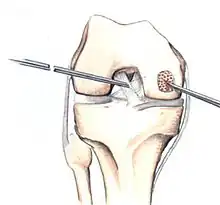

Hinged lesions

Pins and screws can be used to secure flap (sometimes referred to as hinged) lesions.[55] Bone pegs, metallic pins and screws, and other bioresorbable screws may be used to secure these types of lesions.[56]